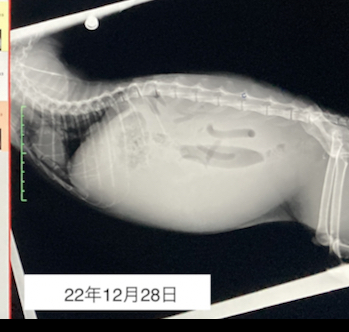

何かがおかしいと思い、年末12月28日に近くの動物病院へと急いで連れて行きました。

そこでレントゲンやエコー、血液検査を行い、かなりの腹水が溜まっている事が分かりました。素人から見ても、レントゲンの腹部は真っ白になっていて腹水がかなりの量あり、深刻なのは一目瞭然でした。

レントゲン写真↓

腹水は粘度性が高く「猫伝染性腹膜炎(FIP)」の可能性がある言われました。 チャイの状態から、残念ながらいつ急変してもおかしくない…お正月を一緒に越せないかもしれないと…